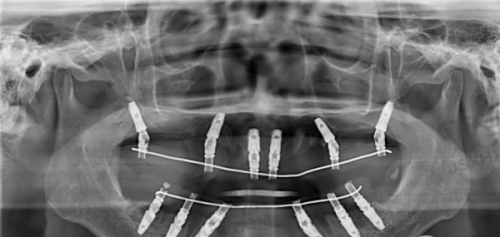

牙齿种植一般分为三个阶段。首先是术前检查和评估,医生会对患者的口腔情况进行全方面检查,包括拍摄X光片、CT等,以确定患者是否适合种植以及种植方案。接着是种植体植入手术,在局部麻醉下,将种植体植入牙槽骨内,然后缝合创口。末尾是安装牙冠,等种植体与牙槽骨完全结合后,再安装愈合基台、取模、制作并安装牙冠。整个过程需要患者积极配合医生,遵循医嘱进行护理。